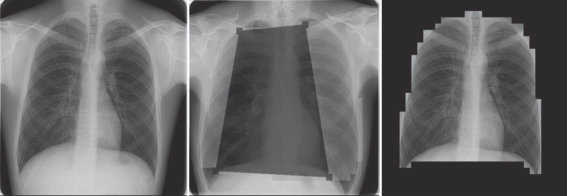

С помощью разработанной вспомогательной нейросети была выполнена предобработка всей исходной Казанской базы рентгеновских снимков легких. Каждый исходный снимок размером 512 × 512 пикселей был поделен на матрицу фрагментов 32 × 32. Полученные фрагменты пропускались через обученную нейросеть и разделялись на классы, дальнейшая обработка проводилась согласно описанному выше алгоритму. Примеры исходного и предобработанного снимков с закрашенной черным цветом не интересующей нас областью представлены на рис. 2. В результате была получена база предобработанных рентгеновских снимков, которая была использована для обучения разработанной ранее [1] основной нейросети. Для оценки эффекта от предобработки снимков было проведено сравнение качества работы основной нейросети в случае использования для обучения исходной необработанной базы снимков, предобработанной базы снимков и предобработанной базы снимков с использованием системы кодирования HSV вместо RGB. Оценивалась тестовая выборка 21 064 фотографий из Казанской базы снимков, по которой отдельно без пересечений проводилось обучение: 10 532 – норма, 10 532 – патологии. Подсчитывалось количество снимков, которые определялись как норма, эта цифра составляла величину уменьшения объема работы врача (КПД системы), и количество снимков с патологией, определявшихся как норма с вероятностью выше уровня доверия, это значение определяет вероятность ошибок нейросети. Для хранения метаданных и базы снимков использовалась СУБД PostgreSQL с репликациями [8].